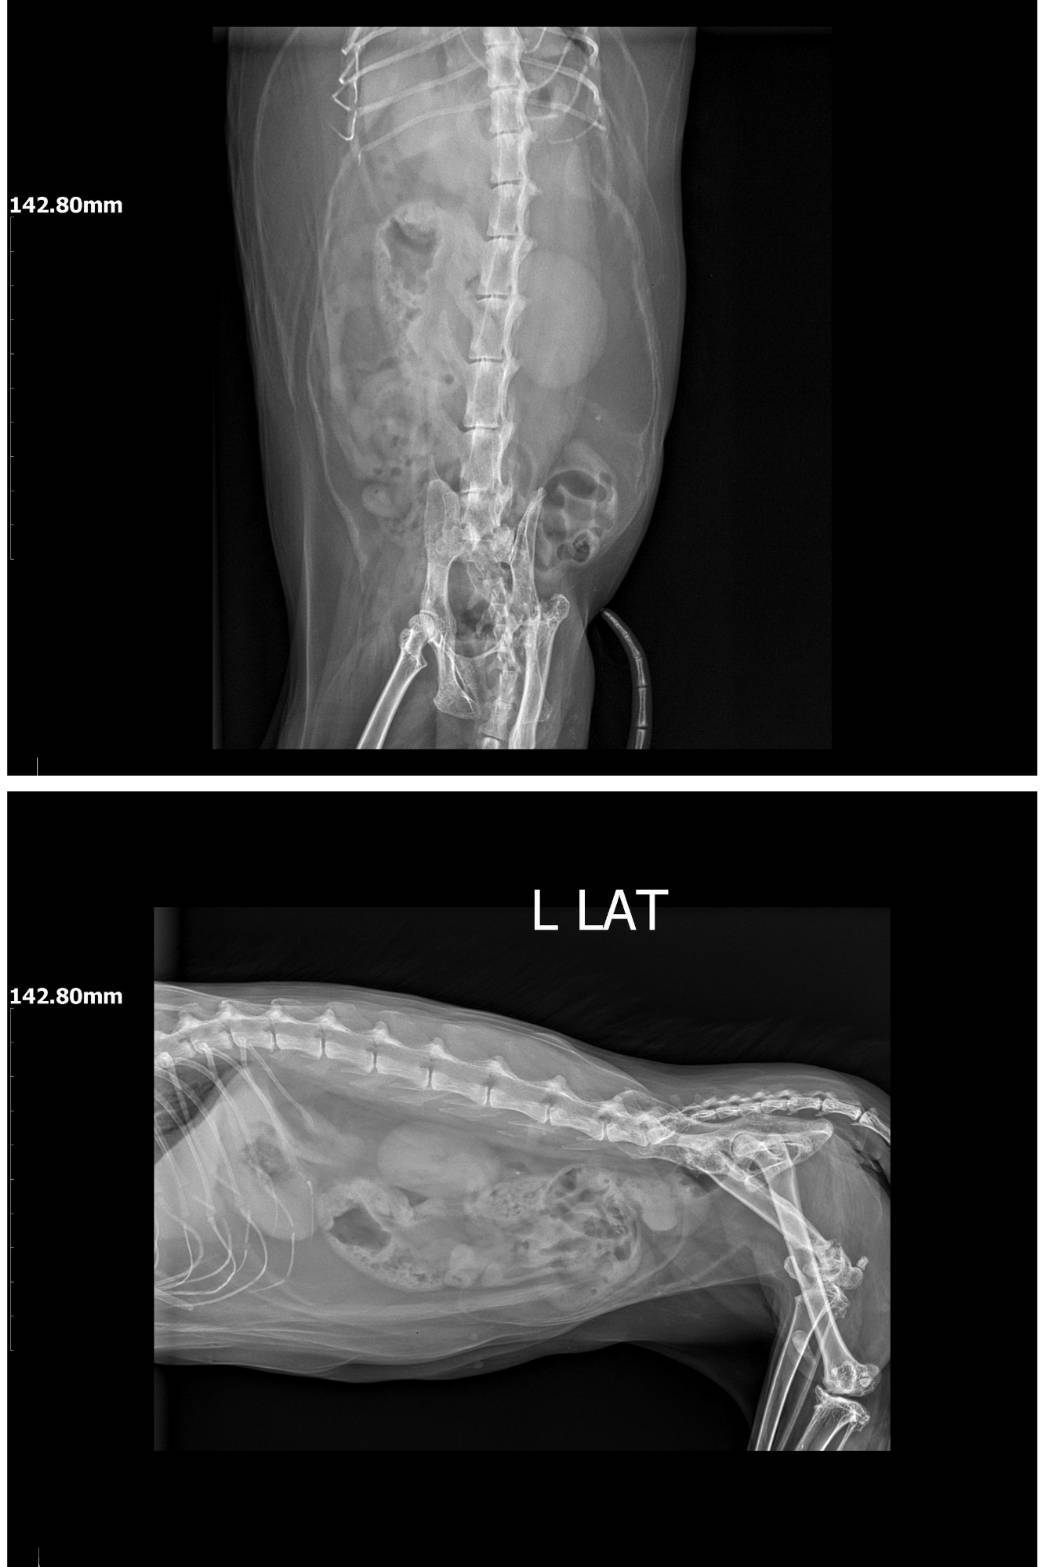

2025年7月1日沐恩回診,因疝氣摸起來變大詢問沐恩約診檢查,原本左側的腹壁疝氣已經定型,目前X光中只有小腸及脂肪疝出,降結腸及膀胱都沒影響,同時只要排便排尿正常就沒問題,但需要控制食量,因為乖妹的體重過重,如果體重沒控制持續上升,將會影響到脂肪突出疝氣的量。

乖妹原本左側的腹壁疝氣已經定型,

目前X光中只有小腸及脂肪疝出,

降結腸及膀胱都沒影響,

同時只要排便排尿正常就沒問題,

但需要控制食量,因為乖妹的體重過重,

如果體重沒控制持續上升,

將會影響到脂肪突出疝氣的量。